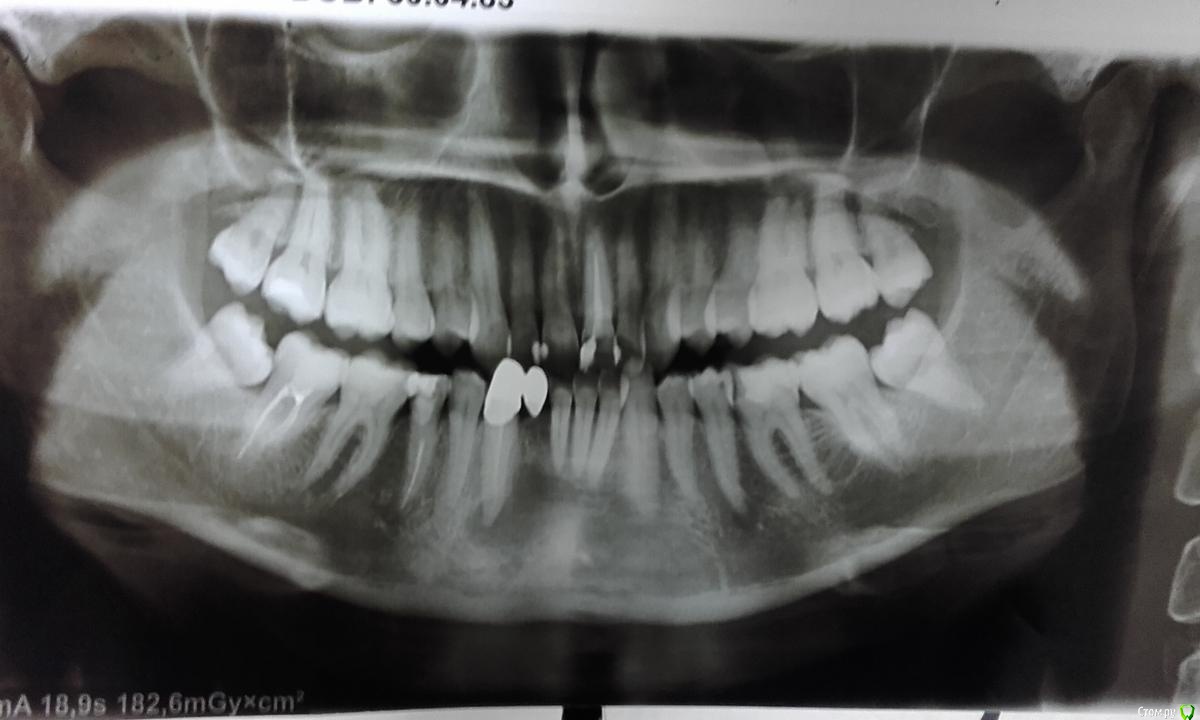

Olga.Ch Опубликовано 11 июня, 2017 Поделиться Опубликовано 11 июня, 2017 Здравствуйте.11 лет назад выбила зуб,поставили консоль с обточкой здорового клыка.До недавнего времени,кроме эстетики ничего не беспокоило.Случайно на рентгене диагностировали кисту.Появились боли в подбородке и небольшая подвижность нижних единиц.Есть ощущение небольшого опущения десны нижних зубов,рецессия.Врачи предлагают перелечивание каналов с установкой временной пломбы сроком на 1 год(при условии их проходимости),либо немедленное удаление,заживление также в течении года и установка уже 2 имплантов.Шансы спасти зуб дают 50/50,естественно без гарантий.На время лечения предлагают сьемный пластмассовый протез.Подскажите,пожалуйста,есть ли шансы спасти когда-то здоровый зуб? Как должно проходить лечение?Есть ли варианты несьемного протезирования на такой длительный срок и до возможной установки имплантов? Ссылка на комментарий

shishok Опубликовано 11 июня, 2017 Поделиться Опубликовано 11 июня, 2017 Думаю,что начать нужно с перелечивания клыка(зуб 43).Передние ,возможно,ни при чем.Проверить их на витальность и наблюдать.ИМХО Ссылка на комментарий

red_butler Опубликовано 12 июня, 2017 Поделиться Опубликовано 12 июня, 2017 +1 перелечить клык, консоль выбросить Ссылка на комментарий